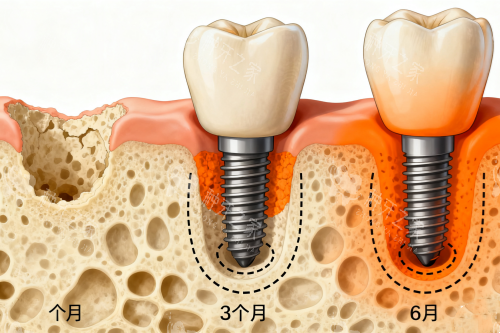

更强的是智能化导板种植技术。医生会根据CBCT扫描的口腔数据,在计算机上模拟种植路径,提前规划好种植体的位置、角度和深度,再通过3D打印制作出个性化导板。

手术时,导板就像“导航仪”,引导医生比较准操作,误差控制在0.1毫米内,比传统“盲种”比较准数十倍。一位在医附大种过牙的张阿姨说:“手术时我全程清醒,就感觉医生拿着工具在导板里操作,一点没慌,术后肿了两天就能正常吃饭了。”